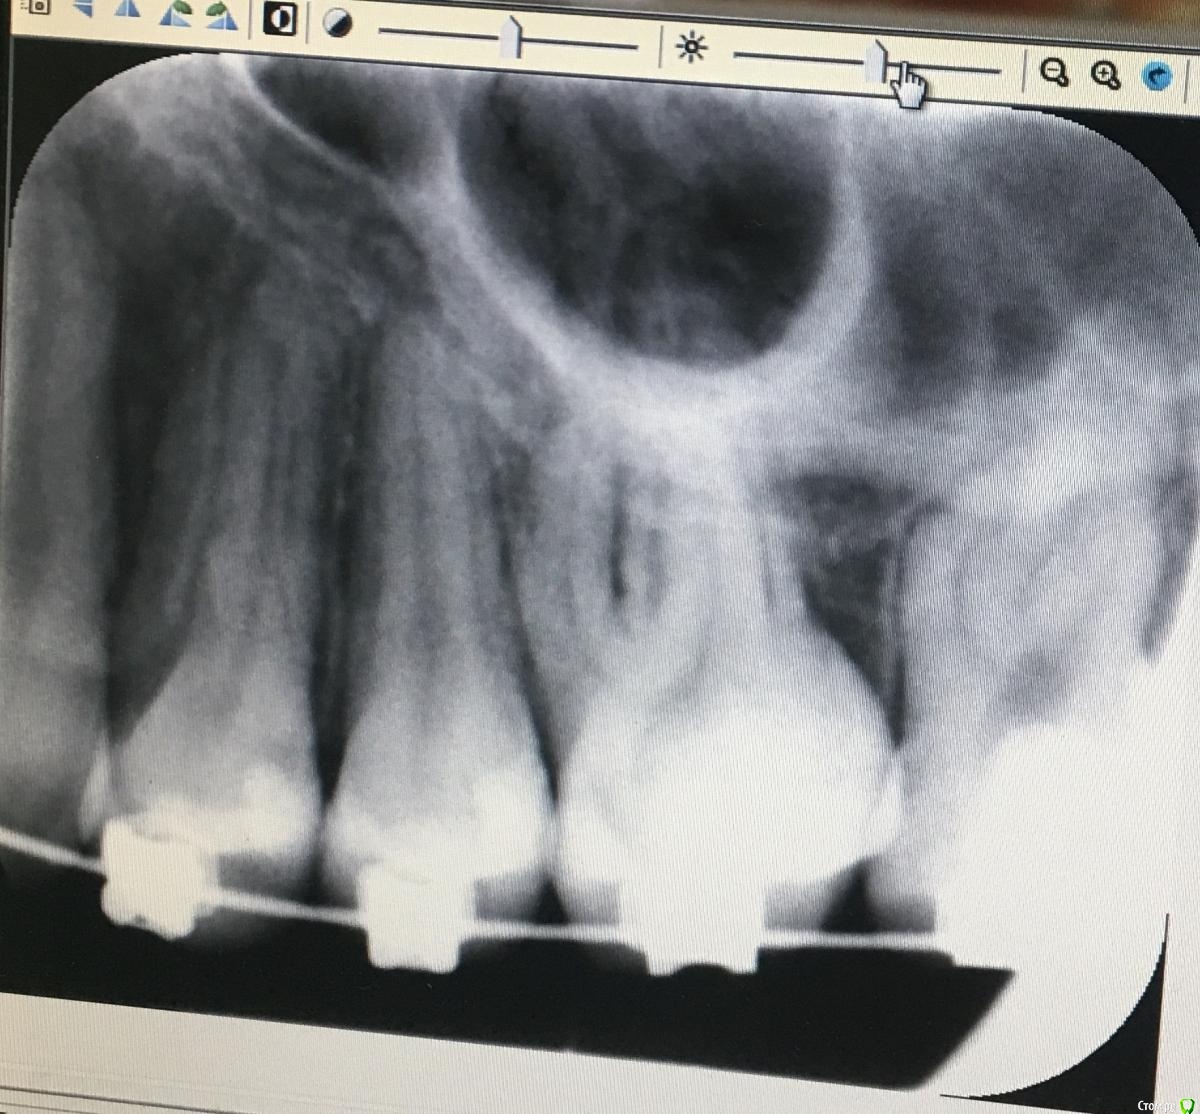

Добрый вечер всем, я ношу брекеты уже 1,5 года. Пришла к врачу проверить зубы на наличие кариеса. Стоматолог начал стучать по зубам и на 5 зубе слева сверху вызвало чувствительность к удару. Сделали снимок. Врач предполагает, что это периодонтит. Этот зуб болит только тогда, когда постучишь. На вид обычный белый зуб. Ортодонт сказала, что можно снять дугу на время, возможно это из-за нагрузки, зуб об зуб. Она освободила мне этот зуб от нагрузки, сказала, что может рассосаться, если рассосётся, то это точно из-за нагрузки. Скажите, похоже это на периодонтит? Я очень сильно переживаю.

post-58572-0-40098100-1608841058_thumb.jpeg